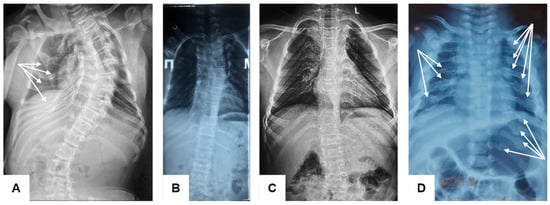

The study noted significant clinical variability among the four unrelated patients with OI Type XI, aged between 2.5 years and 21 years. The most severe course of the disease was observed in patients aged 21 years (F1-P1) and 2.5 years (F4-P4). The age of the first fracture among the examined patients varied from the intrauterine period (F4-P4) to 10 years (F2-P2). The total number of fractures was highest in the individual aged 21 years (F1-P1), and the frequency of fractures per year was higher in the child aged 2.5 years (F4-P4), despite both undergoing bisphosphonate therapy. All examined patients had scoliosis of varying severity, progressing with age. Interestingly, severe scoliosis in patient F1-P1 was accompanied by the preservation of vertebral body height (Figure 1).

Figure 1. Radiographs of the thoracolumbar spine and chest in anterior views of patients with osteogenesis imperfecta Type XI of different ages ((A)—F1-P1, (B)—F2-P2, (C)—F2-P2, (D)—F4-P4): the chest is narrowed, especially in the upper segment; multiple rib fractures (white arrows); scoliosis of varying severity with a tendency to increase with age.